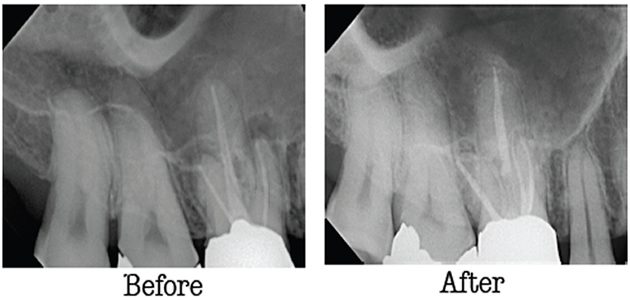

Endodontic Retreatment

With proper care, even teeth that have had root canal treatment can last a lifetime. But sometimes, a tooth that has been treated doesn't heal properly and can become painful or diseased months or even years after treatment. If your tooth failed to heal or develops new problems, you have a second chance. An additional procedure may be able to support healing and save your tooth. If you are experiencing dental pain or discomfort in a previously treated tooth, talk to an endodontist about retreatment.